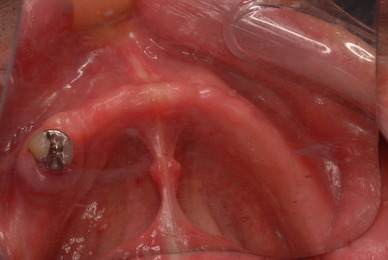

お口の中から差し歯、入れ歯、詰め物を追放しましょう!

口の中の病気を治し、病気を興さない医療を目指します。

二度とお口の中へ変なものを入れなくても済むように

「川崎市の入れ歯なら新丸子西口歯科医院へ」